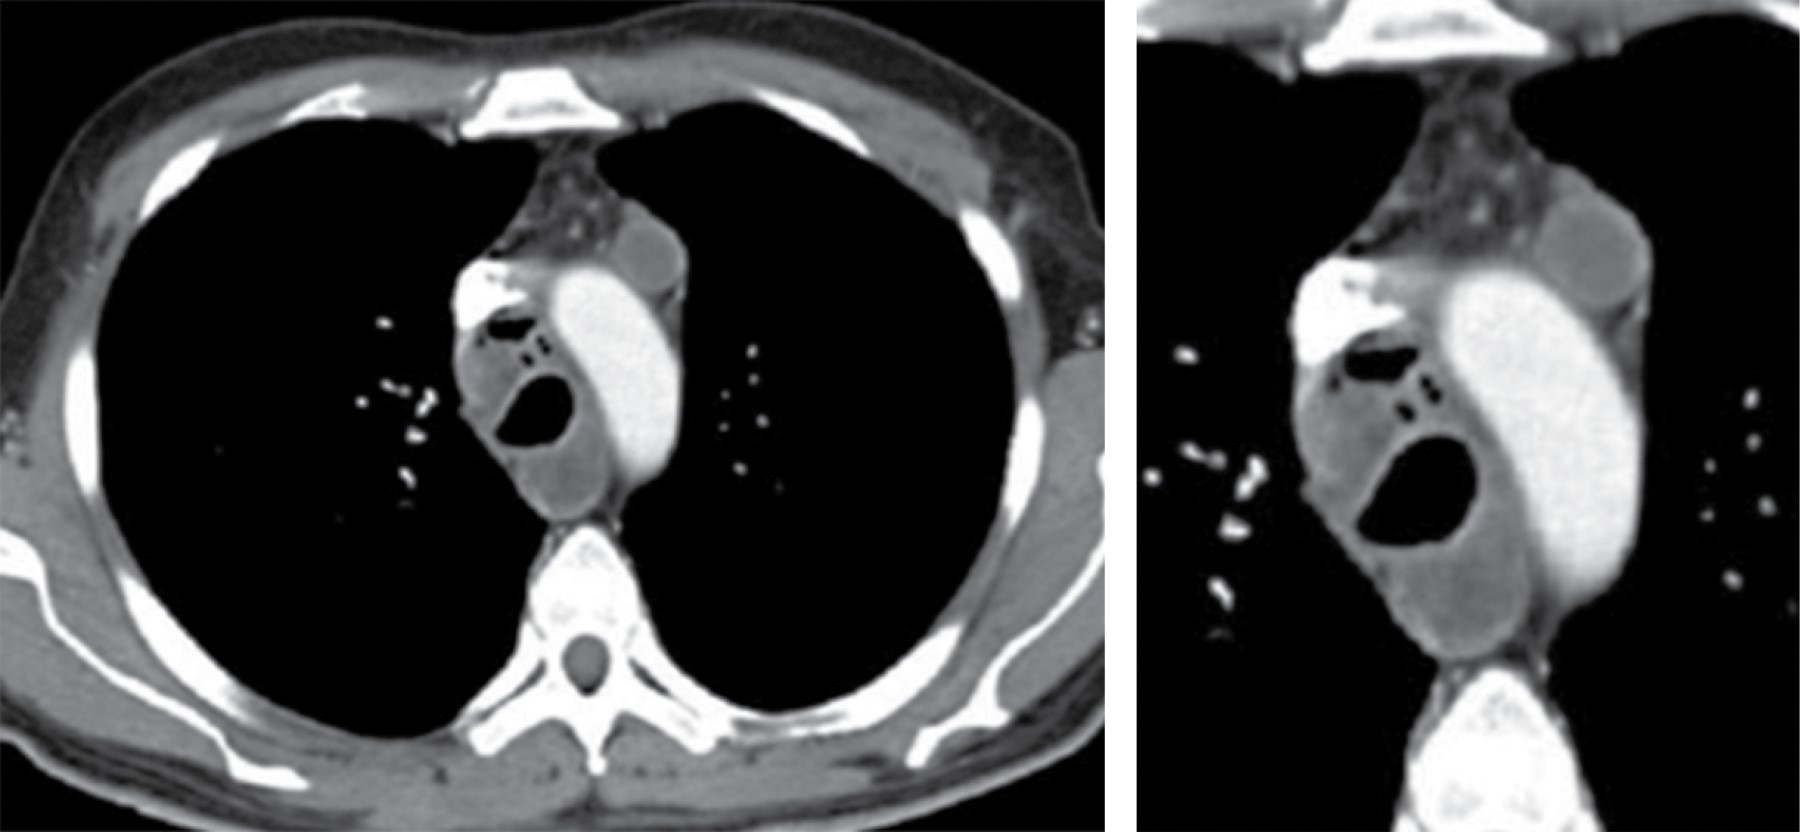

La linfadenopatía mediastinal ocurre en 7% de los adultos con tuberculosis, aunque el crecimiento de ganglios linfáticos es más común en SIDA. La linfadenopatía puede demostrar baja atenuación central, estas áreas de baja densidad dentro de los ganglios linfáticos corresponden a necrosis caseosa (Figura 1).2 La zona paratraqueal derecha es la más común, pero puede afectar el mediastino anterior o el hilio. Los ganglios linfáticos pueden coalescer en masas pobremente definidas y adherirse a las estructuras vasculares adyacentes y estructuras mediastinales.

Otro método de imágenes eficaz para la valoración de los ganglios mediastinales e hiliares es la IRM, cuenta con menor resolución espacial que la TC, pero la utilización de medio de contraste paramagnético hace que pueda identificar fácilmente las adenopatías. Existen niveles mediastinales que pueden ser valorados con mayor facilidad en estudios de IRM, los ganglios que se encuentran en la ventana aortopulmonar se observan en corte coronal, y los ganglios subcarinales que son mejor visibles en corte sagital.